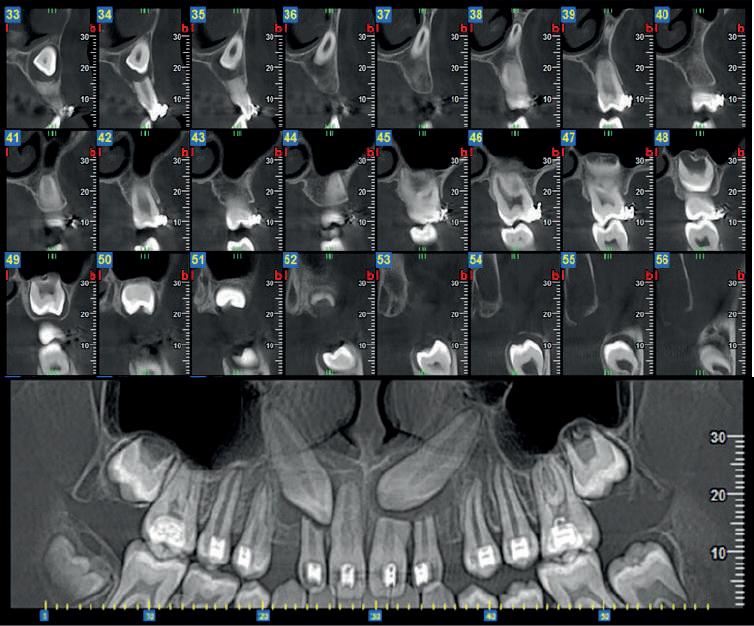

La diagnostica per immagini si avvale di tecniche 2D (Ortopanoramica dentale e full endorale) e 3D (3D Cone Beam Computed Tomography - CBCT).

La 3D CBCT consente la perfetta localizzazione, posizione, versione del canino incluso, la valutazione dei rapporti con gli elementi dentali limitrofi ed eventuali contatti di allarme con le strutture anatomiche critiche (seno mascellare, CNP, fossa nasale, forcazione del premolare superiore).

Le notizie fornite al clinico sono necessarie nella pianificazione della terapia di disinclusione, che può essere ortodontica e/o chirurgica.

Nel presente articolo presentiamo 3 casi di inclusione del canino superiore.

Fig 2 : stesso Paziente. Ricostruzione panorex.

Il 13 è incluso per ostacolo di eruzione relativo alla presenza di minuti denticoli (odontoma composto).

In emiarcata sinistra, come reperto collaterale, si osserva persistenza di 63 ed agenesia di 23.

Fig 3 - Fig 4 : Paz F. aa 12

Il 13 ed il 23 sono inclusi in posizione alta, mesioangolati, con associate ampie cisti follicolari.

Il 13 è visibile dalla sezione radiale 21 alla 26.

La cuspide di 13 è craniale al 12.

Le cisti follicolari assottigliano, e a destra in parte discontinuano, i tavolati corticali vestibolare e palatale.

Si rileva inoltre rizalisi di 12. 21. 22 relative alla estensione delle lesioni cistiche.

Fig 5 - Fig 6 : Paz F aa 16 Ricostruzione panorex e sezioni radiali dell’emiarcata sinistra.

- Il 23 è in trazione ortodontica per inclusione alta in posizione mesio-trasversa, contiguo al pavimento della fossa nasale sinistra ed al pavimento del seno mascellare sinistro.

L’apice radicolare di 23 si impegna nel pavimento del seno mascellare sinistro; la cuspide erompe in versione vestibolare, craniale all’apice radicolare di 24.